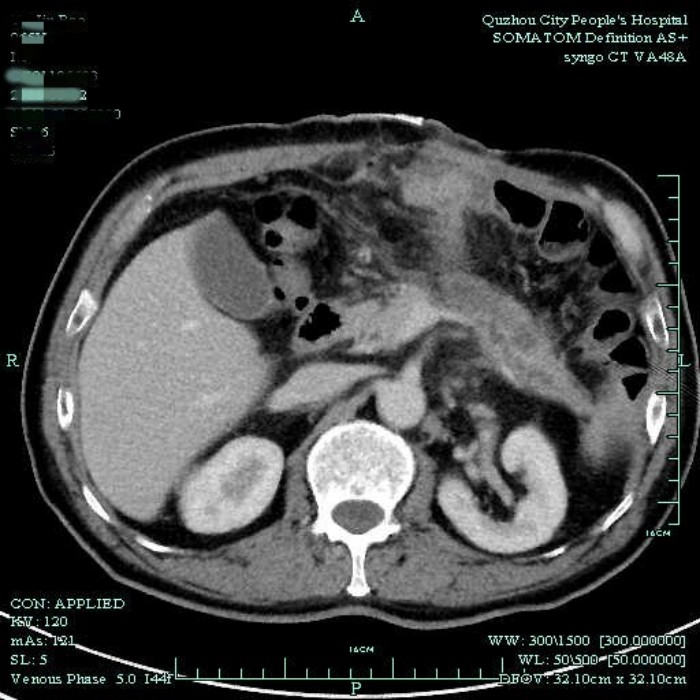

通過電話溝通,醫(yī)生在了解病情后,建議余大伯早點(diǎn)到醫(yī)院治療。入院后,醫(yī)生檢查發(fā)現(xiàn)余大伯腹壁引流管縫隙處已經(jīng)糜爛,形成潰瘍,這是因?yàn)殚L期縫線的牽拉,加上大量的胰液滲漏腐蝕管口的新生組織造成。后來通過CT檢查,發(fā)現(xiàn)胰尾處有一個(gè)巨大囊腫,綜合考慮患者病情后,建議盡早手術(shù)治療。